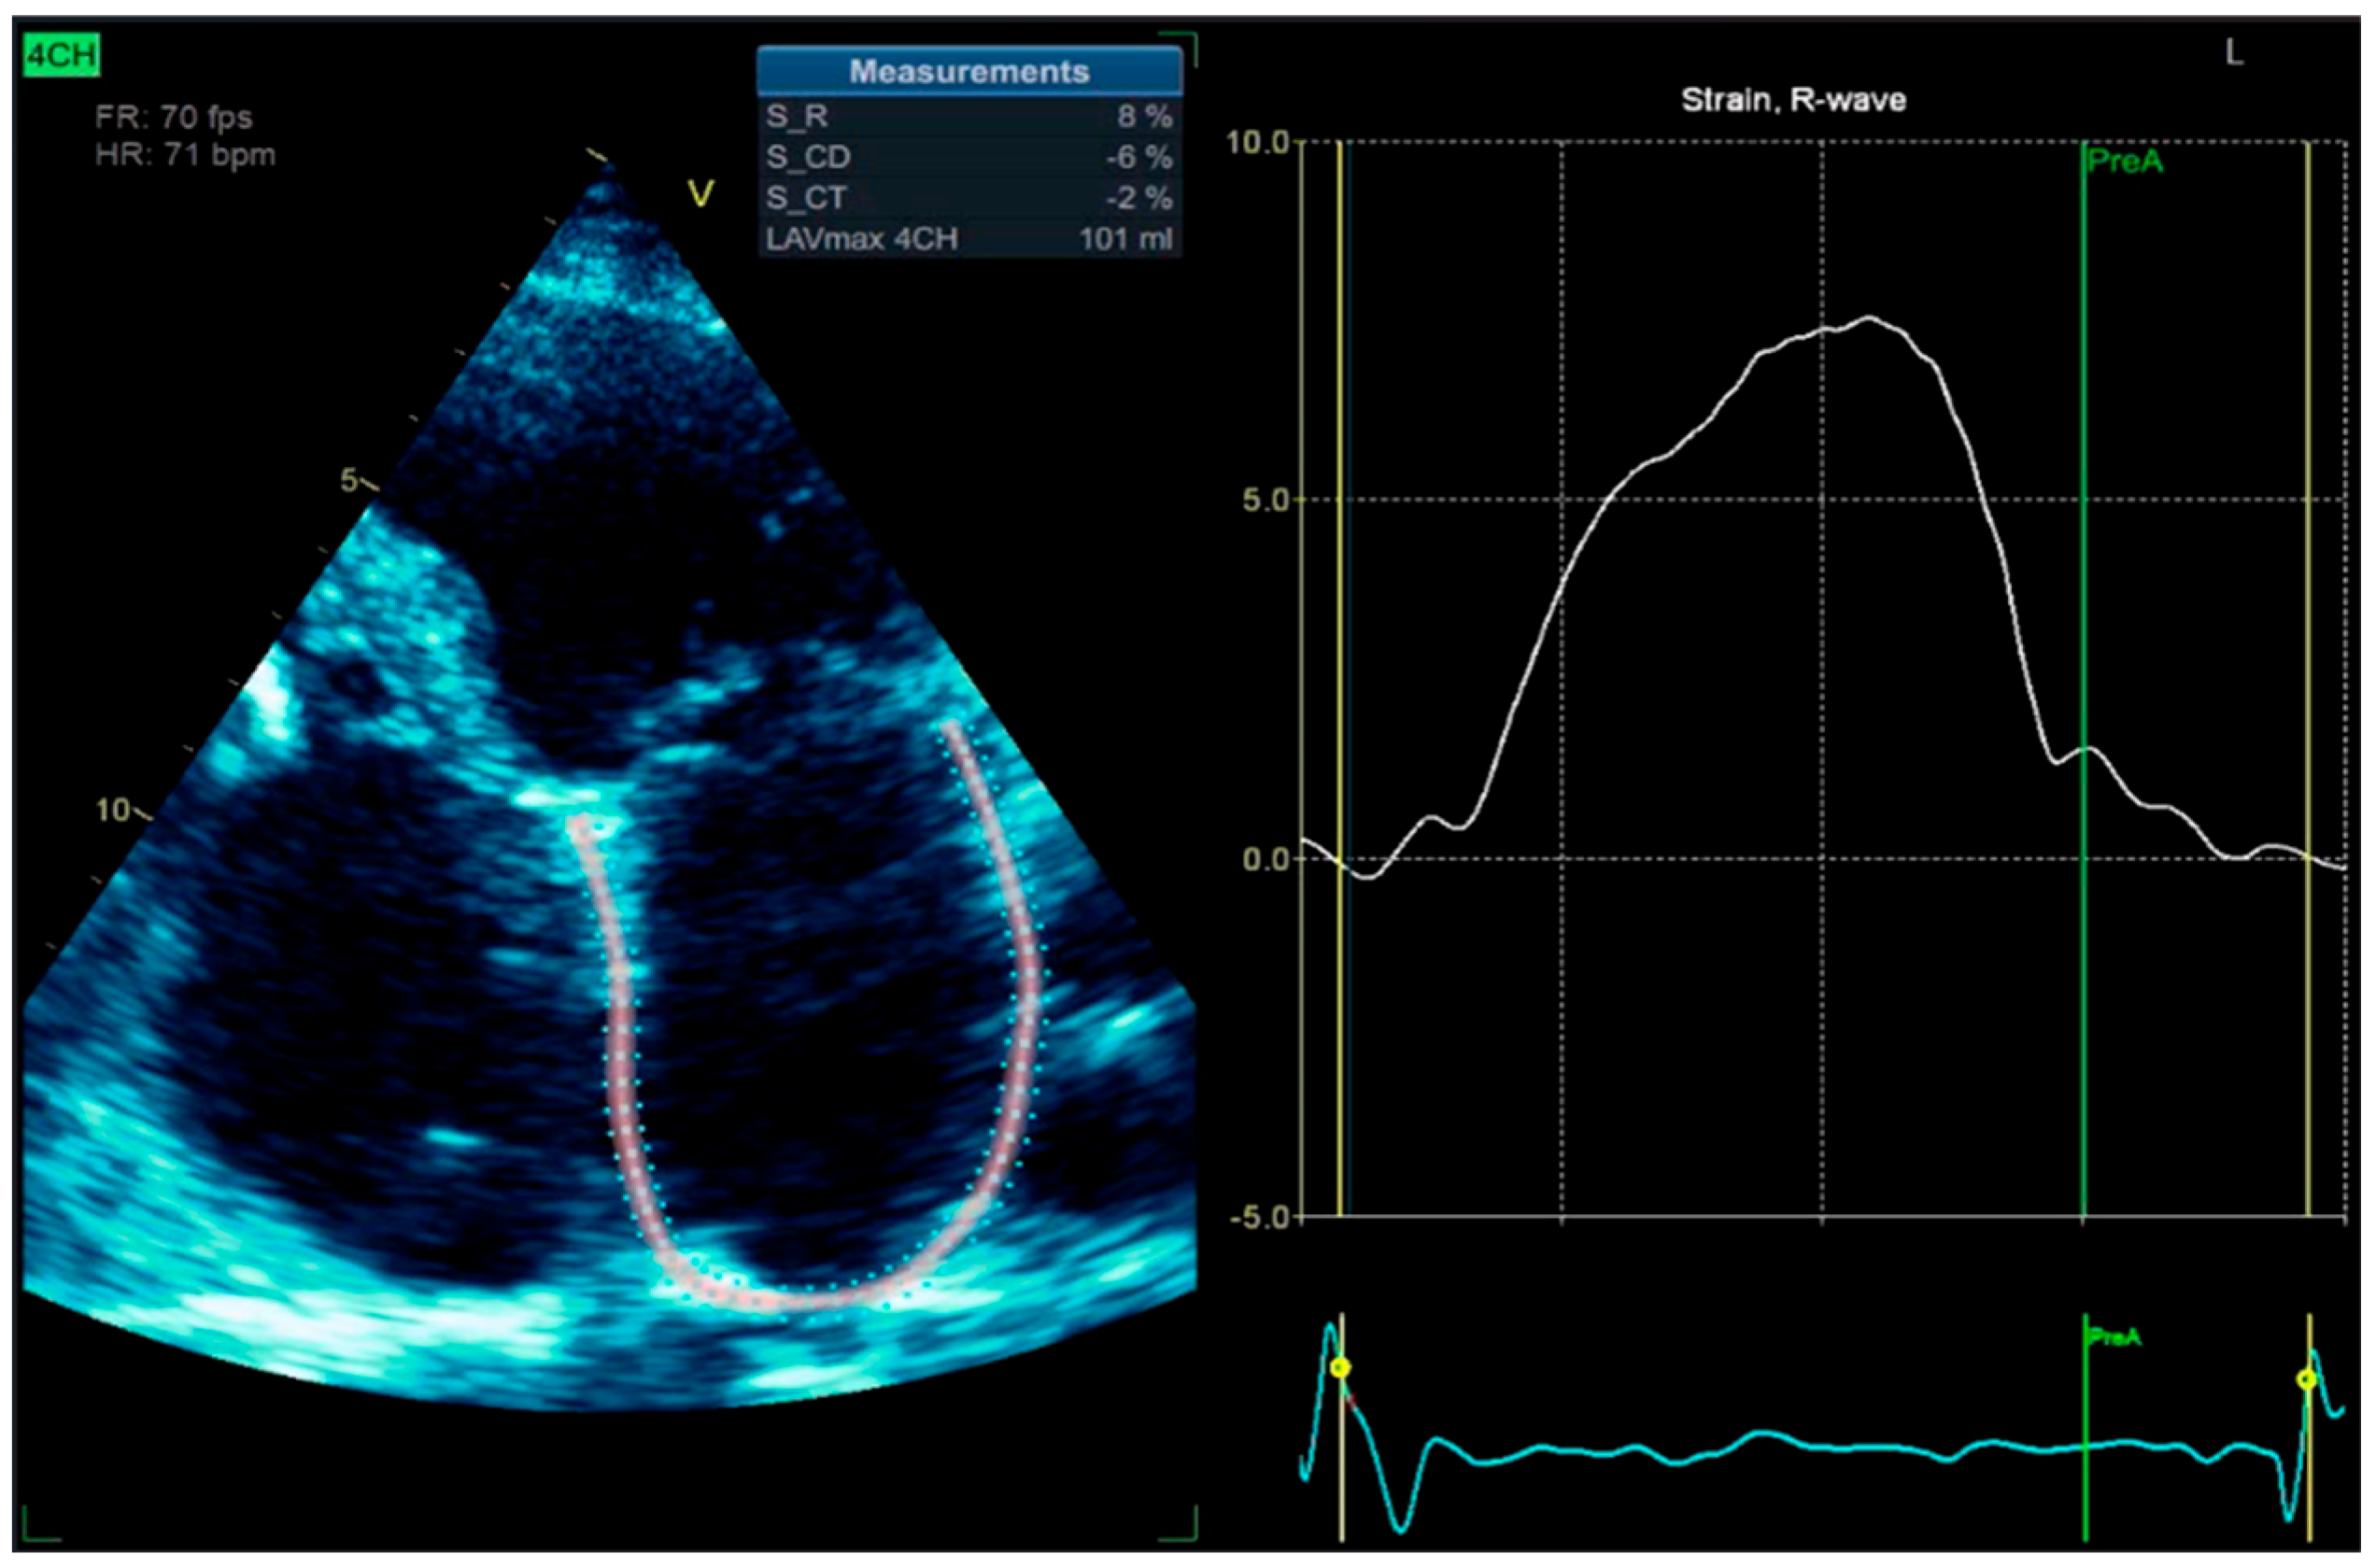

To enhance atrial activity recording, a modified surface ECG was performed using the Lewis lead placement. The Lewis lead is a modified ECG lead configuration designed to enhance the detection of atrial activity, which is particularly useful in identifying P waves during arrhythmias such as atrial flutter or atrial tachycardia [7]. In this setup, the right-arm electrode is placed on the manubrium of the sternum, and the left-arm electrode is placed on the right fifth intercostal space close to the sternum, with the left-leg electrode remaining in its standard position. This orientation essentially aligns the lead to the atrial vector, providing a clearer view of atrial depolarization (Figure 11) [8]. We also performed left atrium strain by the speckle-tracking echocardiography technique, which confirmed atrial stunning with a loss of contraction (LA contraction strain was −2%), a specific change in atrial fibrillation (Figure 12).

Figure 12. 2D-TTE speckle-tracking strain imaging shows enlargement of the left atrium with an increase in the left atrial volume index (LAVi = 101 mL), demonstrating a loss of contractile phase (−2%) and atrial stunning due to atrial fibrillation.

In the context of atrial tachyarrhythmias (ATAs), LA strain is particularly helpful in distinguishing atrial fibrillation from other organized ATAs, such as atrial flutter or atrial tachycardia. Patients with atrial fibrillation typically exhibit significantly reduced LA reservoir and conduit phase, with the absence of contraction phase and reduced global strain values compared to those with other ATAs, reflecting a greater degree of atrial fibrosis and disorganization of the atrial activity. These changes result in impaired LA compliance and function, which can be objectively captured using strain imaging [32,33].